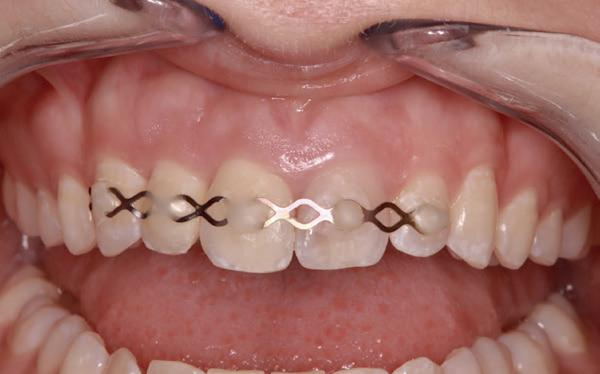

Een week later zie ik de jongedame samen met haar moeder voor een uitgebreid consult en maak ik lichtfoto’s. Deze zijn altijd erg waardevol in dit soort trauma casussen (foto 9).

Meteen na het ongeval is gecontroleerd of de patiënt nog beschermd was tegen tetanus. Ik bespreek de ontstane gebitssituatie; een tot voor kort volledige gave dentitie. Nu een 11 met een horizontale wortelfractuur en een gereplanteerde 21 met een necrotische pulpa. De pulpa van element 11 reageert positief op de koudetest. Uiteraard wordt er een afwachtend beleid in gesteld.

Gelukkig zijn de patiënt en haar moeder erg nuchter en begrijpen de situatie volkomen. In dezelfde afspraak wordt er gestart met een endodontische behandeling van element 21. Plaats hierbij geen cofferdamklem op het element zelf. Deze staat nog niet vast genoeg.

Een afspraak voor over drie weken wordt gemaakt om de spalk te verwijderen en de endodontische behandeling af te maken. Het advies is om de elementen weer normaal te gaan gebruiken en alles zeer goed te poetsen. Door het ‘normale’ gebruik bewegen de elementen en dit bevordert de genezing. Hetzelfde advies als na een autotransplantatie van een gebitselement (foto 10 en 11).

9. Situatie één week na het trauma.